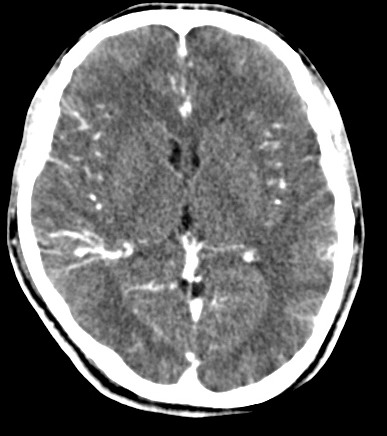

男,31岁,头疼就诊,其他不祥。

考虑右颞叶脑血管畸形伴出血。avm可能大,建议dsa。

平扫见右颞叶、右侧脑室后角旁略高密度影,增强未见明显病灶,基本正常。不放心做mri检查

病灶呈略高密度,周围伴环形水肿,无强化/无异常av影........

考虑为:1.脑内小血肿?   2.脑灰质异位?   建议mri检查........

考虑右颞叶脑血管畸形伴出血。考虑静脉血管瘤,深部型的,avm不除外,建议dsa。